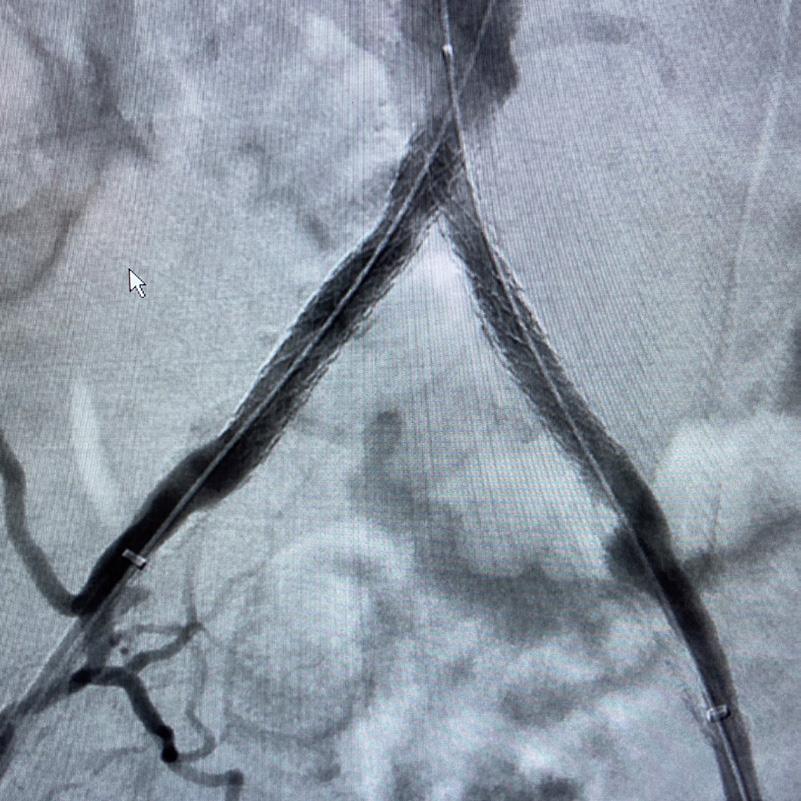

Case 2: The Shockwave M5+ tackles 90% stenosis of the distal SFA

The patient is a 75-year-old man with a history of hypertension, hyperlipidemia, CAD, chronic kidney disease and diabetes mellitus, who presents with a non-healing wound of the right lower extremity for three months. He had undergone diagnostic work—his ankle-brachial index (ABI) was found to be 0.73 with a toe pressure of 50mmhg, and a duplex ultrasound revealed a densely calcified superficial femoral artery (SFA) stenosis of 90%.

He was taken to the cath lab and underwent a right lower-extremity arteriogram. This confirmed a 90% stenosis of the distal SFA, with normal three-vessel run off. Due to the heavy calcium, we opted for a Shockwave M5+ 6x60mm and delivered 200 pulses to the lesion. There was no appreciable residual stenosis at the completion of the procedure, and his post-procedure ABI improved to 1.

This is a great example of how IVL can be used as a standalone therapy without the need for adjunctive treatment.

Figure 1. Pre-procedural angiogram

Figure 2. Pre-procedural angiogram

Figure 5. Final angiogram

Figure 2. IVL treatment angiogram

Figure 3. Post-IVL angiogram